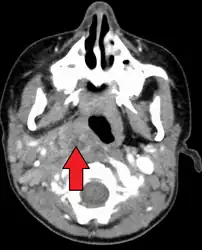

A computed tomography (CT) scan is the definitive diagnostic imaging test.[6]

X-ray of the neck 80% of the time shows swelling of the retropharyngeal space in affected individuals. If the retropharyngeal space is more than half of the size of the C2 vertebra, it may indicate retropharyngeal abscess.[7]

Large retropharyngeal abscess as seen on CT